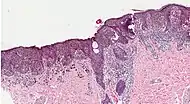

SN TypeFeaturesIncidence[82][notes 1]PhotographMicrograph

1. Superficial spreading melanoma Melanoma cells with nest formation along the dermo-epidermal junction. 70%

2. Nodular melanoma Grows relatively more in depth than in width. 15% - 20%

3. Lentigo maligna melanoma Linear spread of atypical epidermal melanocytes as well as invasion into the dermis.[83] 5% - 10%

4. Acral lentiginous melanoma Continuous proliferation of atypical melanocytes at the dermoepidermal junction.[84] 7% - 10%